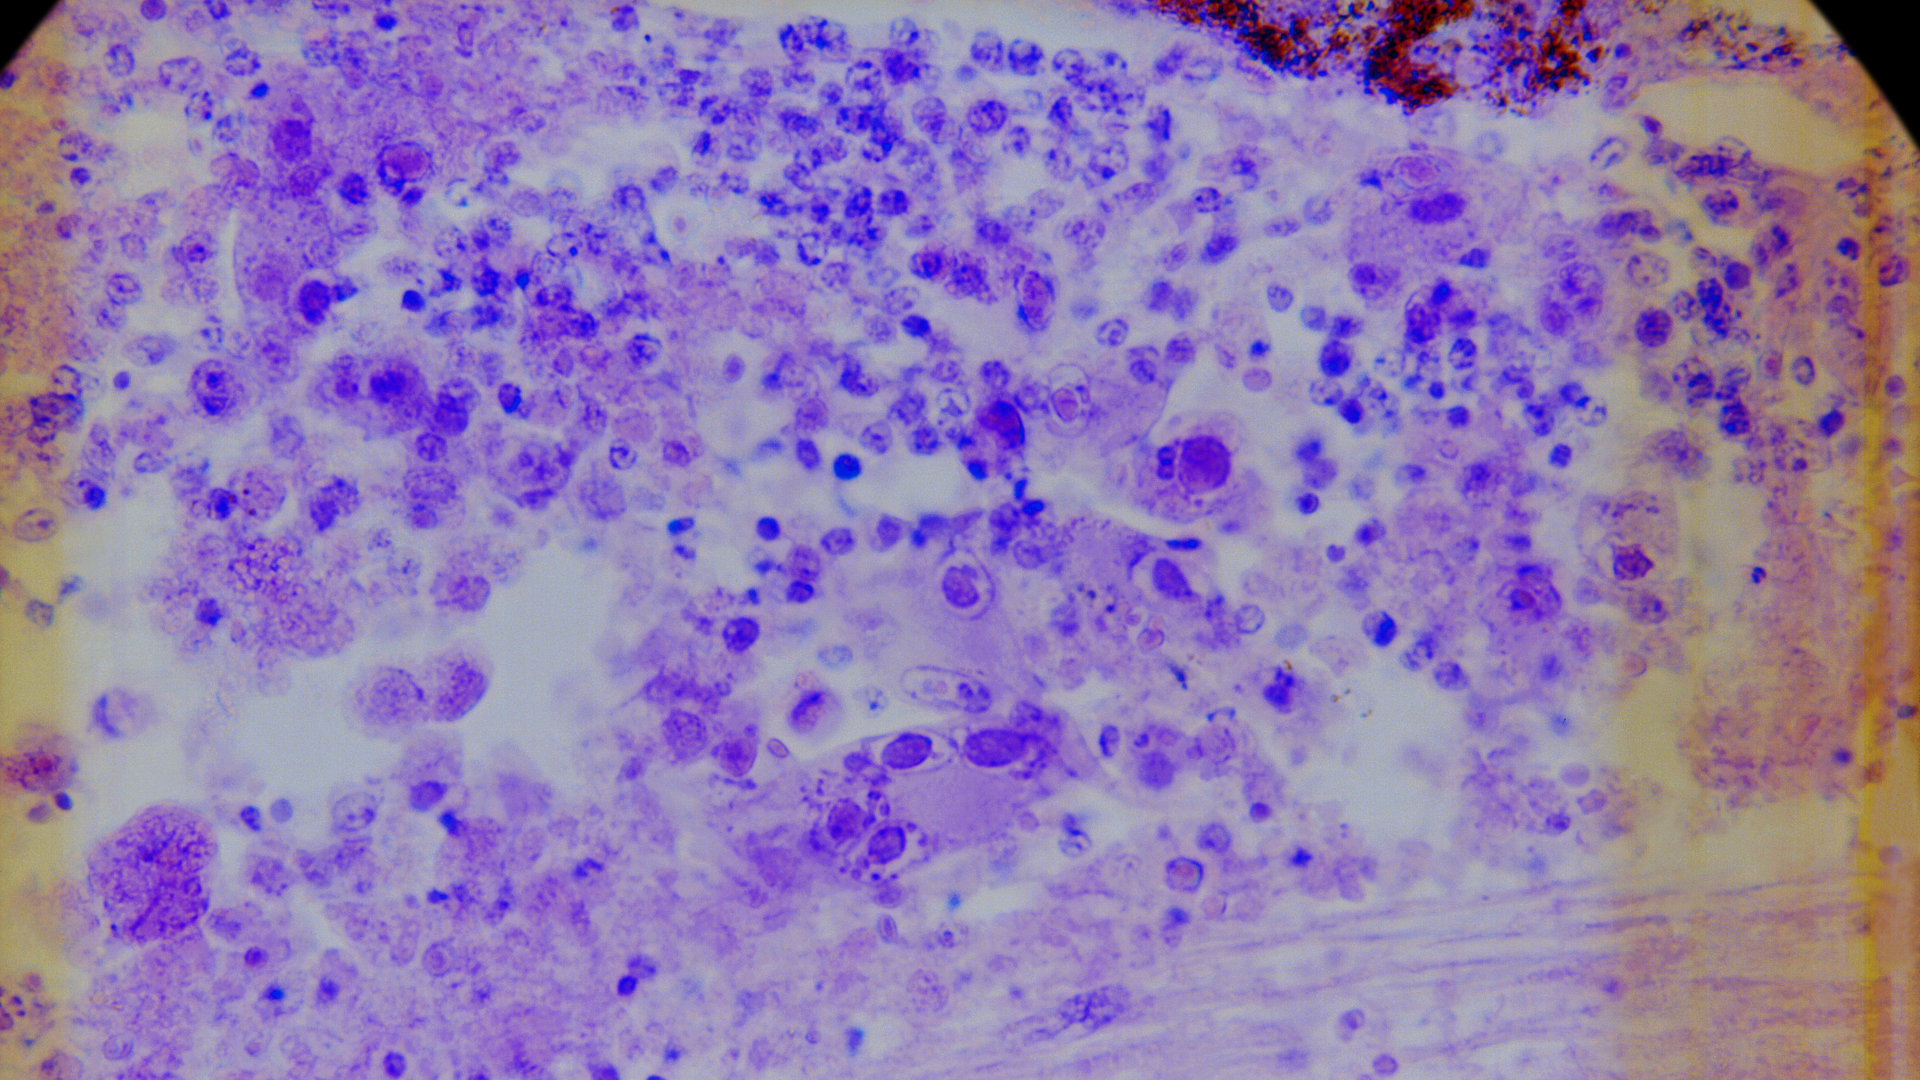

DLBCL is the most common type of lymphoma, accounting for 40% of lymphoma cases worldwide. The NIH said this fast-growing cancer affects B cells, a type of white blood cell, and usually starts in the lymph nodes. People with DLBCL are typically treated with a chemotherapy regimen known as R-CHOP that includes cyclophosphamide, doxorubicin, vincristine, prednisone, and the monoclonal antibody rituximab. But R-CHOP is not effective for all people with DLBCL.

In the 2000s, to better understand individual variation in treatment response, researchers analyzed the patterns of gene activity in DLBCL tumors. They discovered that there are three molecular subgroups of DLBCL: germinal center B cell-like (GCB), activated B cell-like (ABC), and unclassified. Researchers later found that these subgroups respond differently to chemotherapy. More recently, researchers showed that the ABC and GCB subgroups can be further divided into seven genetic subtypes that also respond differently to chemotherapy.

What was unclear from the PHOENIX trial was whether all younger patients with non-GCB DLBCL benefited from ibrutinib, or if there was greater benefit for patients with certain genetic subtypes. To gain insights into this question, researchers performed genetic analyses on tumor samples from 773 of the 838 participants and determined their subtypes using an algorithm called LymphGen that Dr. Staudt developed with his NCI colleague George Wright, Ph.D.